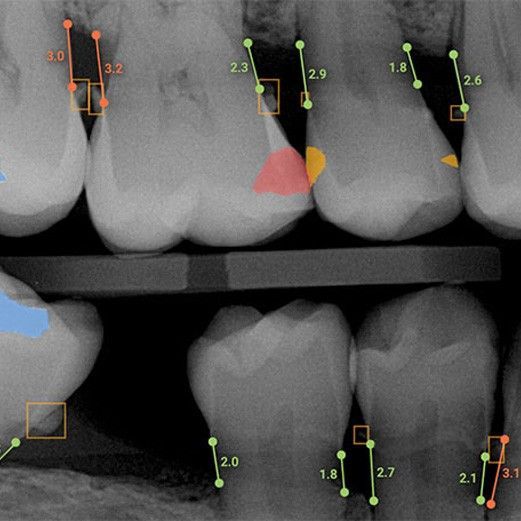

Pearl

Pearl is an AI that was trained using countless dental X-rays to help it identify the earliest signs of many potential issues, including decay and bone loss. Our dentists use it to get a second opinion when analyzing X-rays. This essentially means that a patient’s radiographs benefit from having two sets of expert eyes on them. Best of all, this technology helps our team find potential problems and treating them well before they cause any pain or damage.